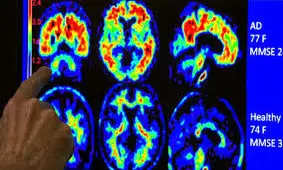

متخصصان علوم پزشکی در آمریکا بر اساس شواهد موجود بر این باورند که مصرف داروی آلزایمر مدتها قبل از بروز علائم آن…